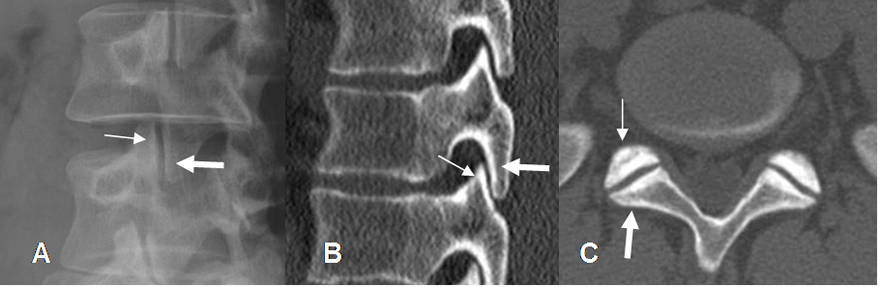

Las articulaciones intervertebrales están compuestas por las facetas articulares. La anterior corresponde a la de la vértebra inferior y la posterior a la de la vértebra superior. El ancho normal del espacio articular en su parte media, es entre 2 y 4 mm. Se habla de estenosis, cuando el espacio es menor de 2 mm. (11). (Fig 20, 21 y 22).

Fig 21. Articulaciones intervertebrales lumbares.

A: Rx oblicua, B: TAC reconstrucción sagital y C: TAC axial. Articulaciones intervertebrales normales. La faceta anterior corresponde a la vértebra inferior (Flecha delgada) y la posterior a la superior. (Flecha gruesa).